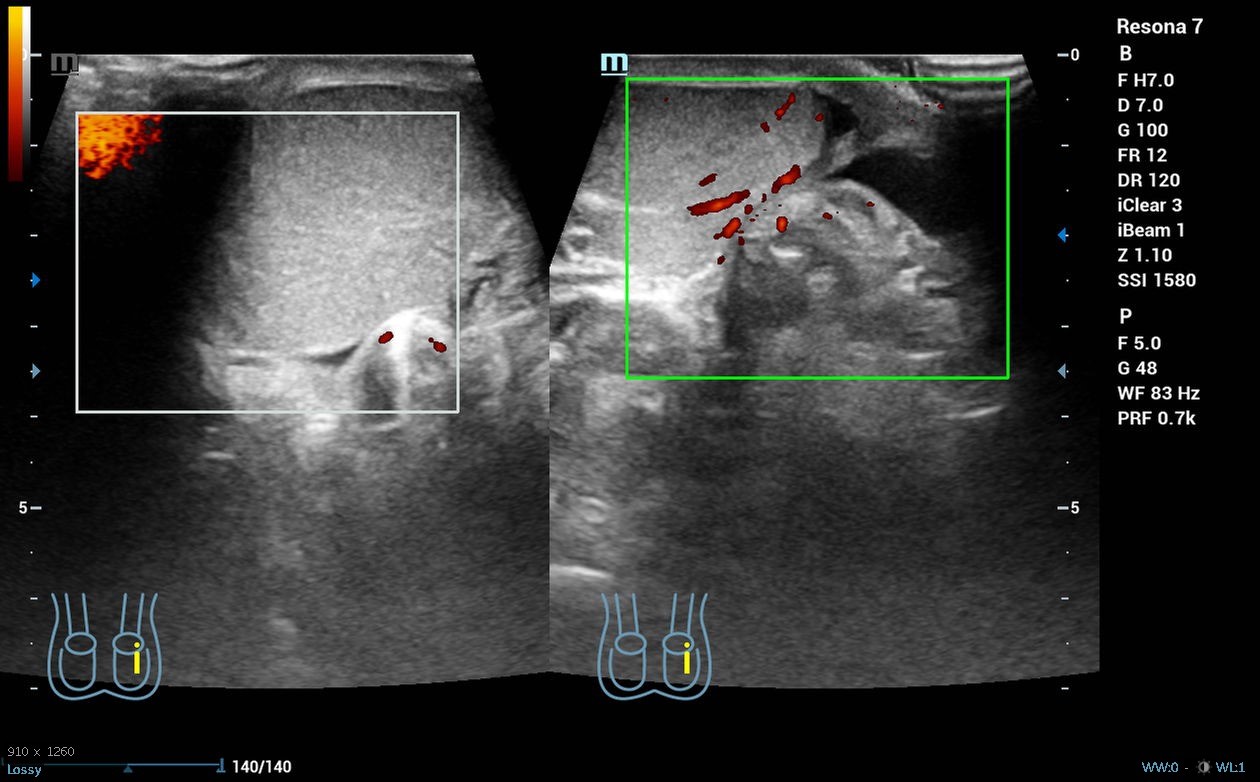

Hombre de 19 años sin antecedentes de interés que acude a la guardia del centro de salud por dolor súbito en el testículo derecho desde las 04.00 h que le ha despertado, asociado a náuseas y vómitos, sin otra clínica infecciosa o traumática acompañante. A la exploración física presenta abdomen normal, pero teste izquierdo ascendido y horizontalizado, doloroso a la palpación, con discreto aumento de tamaño o cambios en temperatura, con signo de Prehn negativo y reflejo cremastérico ausente en lado izquierdo. Se realiza ecografía clínica, donde se objetiva testículo izquierdo aumentado de tamaño con morfología y ecoestructura normal, pero con ausencia de flujo power-Doppler en su interior, ligero hidrocele y aparente giro del cordón espermático en su porción distal.

Derivación hospitalaria urgente, donde se corroboran los hallazgos de la ecografía clínica y se realiza detorsión quirúrgica.